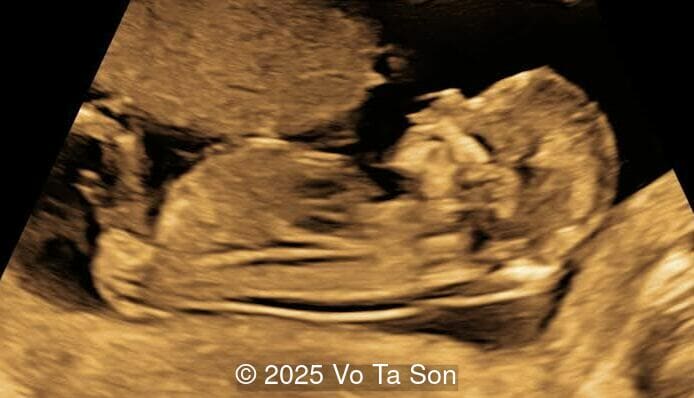

- Open spina bifida in the sacral region with dry brain and crash sign, BS/BSOB >1, direct lesion at sacral coccygeal spine